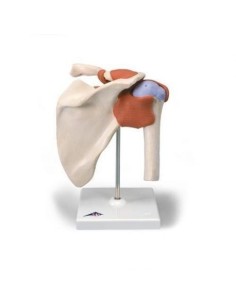

Dal cranio in 22 parti con incastri magnetici ai modelli di colonna vertebrale, da quelli di articolazioni a quelli di cuore, ogni pezzo della nostra collezione è progettato per un’immersione totale nello studio dell’anatomia umana. I nostri modelli, realizzati tramite scansioni di ossa vere, garantiscono un’esperienza tattile autentica e una fedeltà di peso quasi identica agli originali.